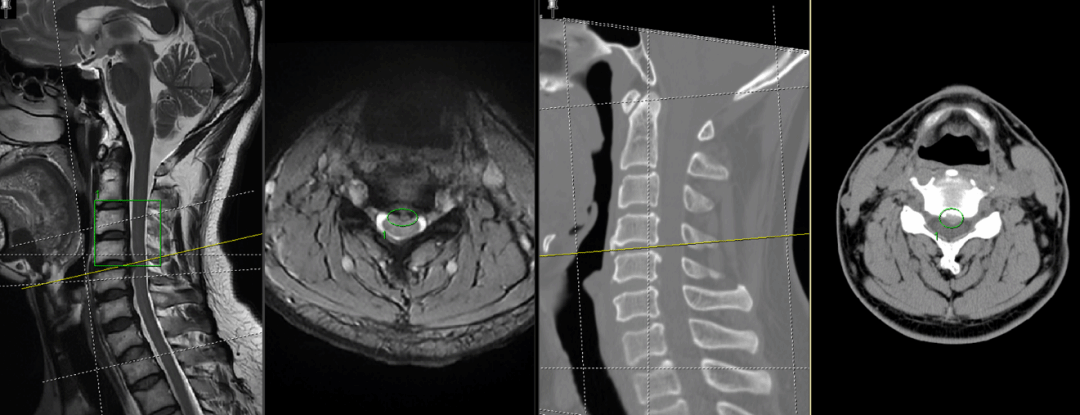

患者范先生,39岁,男性,主诉为:颈肩痛伴左上肢麻木3个月,加重伴左上肢无力1月。3个月前患者无明显诱因出现颈肩部疼痛伴左上肢麻木,伴走路不稳,足底踩棉感,就诊于外院,行颈椎MRI,考虑“脊髓型颈椎病”,给与保守治疗后症状无明显改善,1月前症状加重,出现左上肢无力,麻木感加重。查体:颈椎生理弯曲存在,主动活动轻度受限,颈部后仰时,右侧Hofmann征阳性,双侧Rossolimo征阳性,双侧臂丛神经牵拉试验阴性,双侧椎间孔挤压试验阴性,余四肢感觉、肌力肌张力及反射未见异常。患者术前CT及核磁结果如下图所示:

患者术前CT及核磁结果